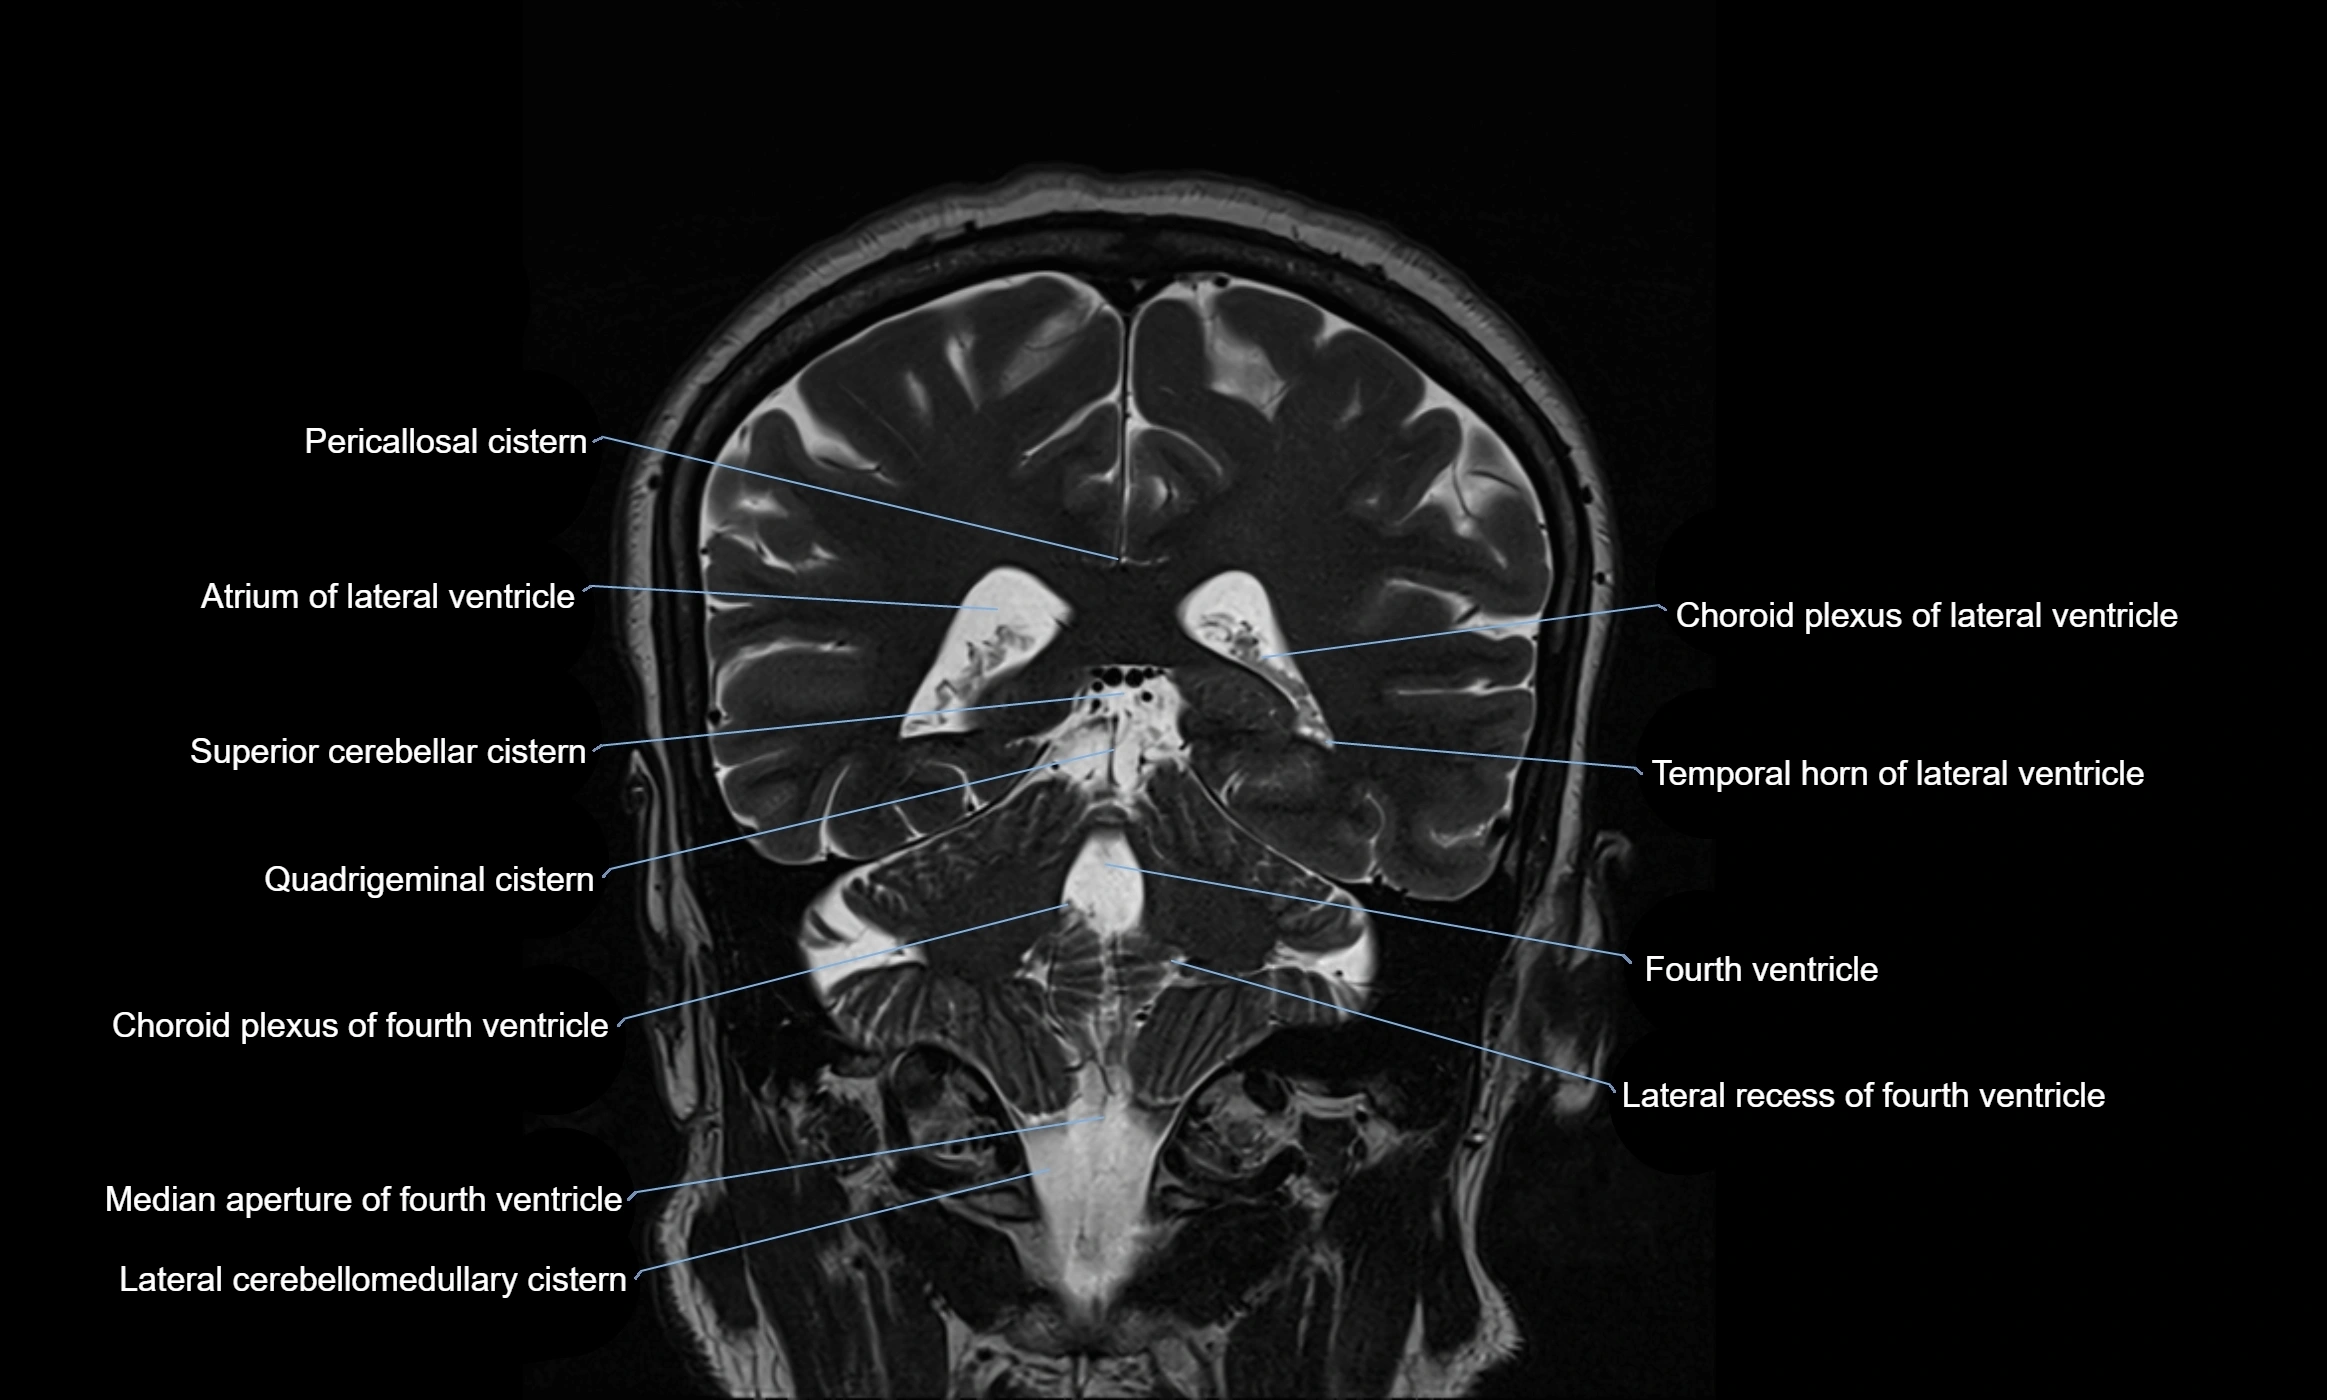

MRI images

image